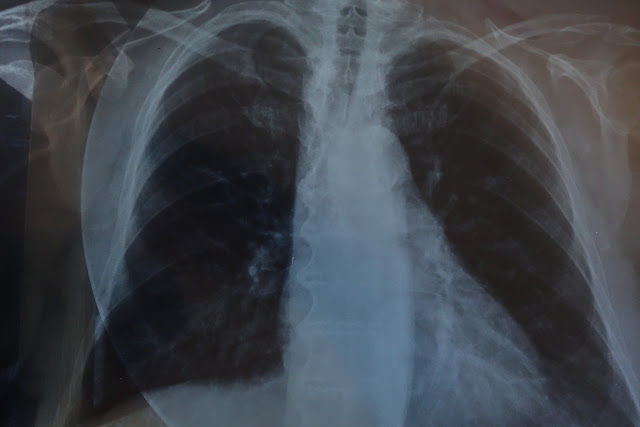

Άνδρας 65 ετών παραπονούμενος για εύκολη κόπωση (καταβολή δυνάμεων) και νυκτερινή δύσπνοια. Η αντικειμενική εξέταση δεν είχε σημαντικά ευρήματα, εκτός από ελαττωμένη ένταση του πρώτου τόνου.

Τι βλέπουμε στην ακτινογραφία και ποια είναι η κύρια διαγνωστική κατεύθυνση και η ενδεδειγμένη περαιτέρω διερεύνηση ;

Αυξημένες διαστάσεις καρδιακής σκιάς με αυξημένη προβολή του αριστερού κάτω τόξου αυτής και χαμηλή θέση της καρδιακής κορυφής, όπως παρατηρείται σε διάταση της αριστερής κοιλίας. Ελαφρά διόγκωση των πνευμονικών πυλών, όπως αυτή που παρατηρείται σε αγγειακή συμφόρηση δηλαδή σε διάταση των πνευμονικών φλεβών λόγω αυξημένης πνευμονικής φλεβικής πίεσης. Εικόνα εντονώτερης απεικόνισης του πνευμονικού αγγειακού δικτύου (λόγω διάτασης των πνευμονικών αγγειακών κλάδων). Η όλη εικόνα συνηγορεί υπέρ διάτασης και ελαττωμένης συστολικής απόδοσης της αριστερής κοιλίας, με συχνότερες αιτίες την ισχαιμική καρδιοπάθεια, τη διατατική μυοκαρδιοπάθεια και την υπερτασική καρδιοπάθεια όταν αυτή είναι σε προχωρημένο στάδιο και έχει οδηγήσει σε καρδιακή ανεπάρκεια. Άλλη αιτία διάτασης της αριστερής κοιλίας είναι η σοβαρή ανεπάρκεια της αορτικής βαλβίδας (αλλά τότε συνήθως υπάρχει και εικόνα διάτασης της ανιούσας αορτής, που δεν παρατηρείται σε αυτή την περίπτωση). Μια άλλη αιτία είναι η σοβαρή ανεπάρκεια της μιτροειδούς βαλβίδας, (αλλά τότε στην ακτινολογική εικόνα κυριαρχούν τα σημεία διάτασης του αριστερού κόλπου με κύρτωση και αυξημένη προβολή του τόξου του ωτίου του αριστερού κόλπου κάτω από το στέλεχος της αριστερής πνευμονικής αρτηρίας και με αμβλεία γωνία μεταξύ των δύο κύριων βρόγχων, εικόνα που εδώ δεν παρατηρείται σε τόσο έντονο βαθμό). Αυξημένες διαστάσεις της καρδιακής σκιάς παρατηρούνται και σε μεγάλη περικαρδιακή συλλογή, αλλά τότε συνήθως δεν υπάρχει σαφής διάκριση των τόξων της καρδιακής σκιάς (σχήμα καρδιάς που θυμίζει χαρτοσακούλα) γεγονός που εδώ δε συμβαίνει.

Ο περαιτέρω έλεγχος σε τέτοιες περιπτώσεις γίνεται με υπερηχογράφημα καρδιάς προκειμένου να ελεγχθεί η συσταλτικότητα της αριστερής κοιλίας και η λειτουργία των καρδιακών βαλβίδων και σε περίπτωση ελαττωμένης συσταλτικότητας μπορεί να χρειασθεί περαιτέρω έλεγχος με σπινθηρογράφημα μυοκαρδίου ή στεφανιαιογραφία, προκειμένου να διαπιστωθεί αν υπάρχει στεφανιαία νόσος ως υποκείμενη αιτία. Σε αυτή την περίπτωση υπερηχογραφικά διαπιστώθηκε διάχυτη σοβαρή ελάττωση της συσταλτικότητας σημαντικά διατεταμένης αριστερής κοιλίας και πιο ήπια διάταση του αριστερού κόλπου. Η στεφανιαιογραφία δεν έδειξε σημαντικές στενώσεις των στεφανιαίων αρτηριών (μόνο αθηρωματική πλάκα που προκαλούσε στένωση 40-50 % στη μεσότητα του πρόσθιου κατιόντα κλάδου, αιμοδυναμικά μη σημαντική). Η τελική διάγνωση ήταν διατατική μυοκαρδιοπάθεια.